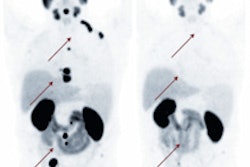

In 1999, Townsend and colleagues introduced the combined PET/CT scanner, which was rapidly adopted and utilized in the nuclear medicine and molecular imaging field.